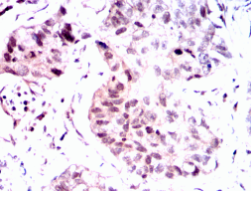

PGR Mouse Monoclonal antibody[2C11F]

PGR: progesterone receptor. This gene encodes a member of the steroid receptor superfamily. The encoded protein mediates the physiological effects of progesterone, which plays a central role in reproductive events associated with the establishment and maintenance of pregnancy. This gene uses two distinct promotors and translation start sites in the first exon to produce two isoforms, A and B. The two isoforms are identical except for the additional 165 amino acids found in the N-terminus of isoform A only, and mediate their own response genes and physiologic effects with little overlap. The location of transcription initiation for isoform B has not been clearly determined.

Immunogen:    Purified recombinant fragment of PGR (aa731-909) expressed in E. Coli.

IHC    1/200 - 1/1000